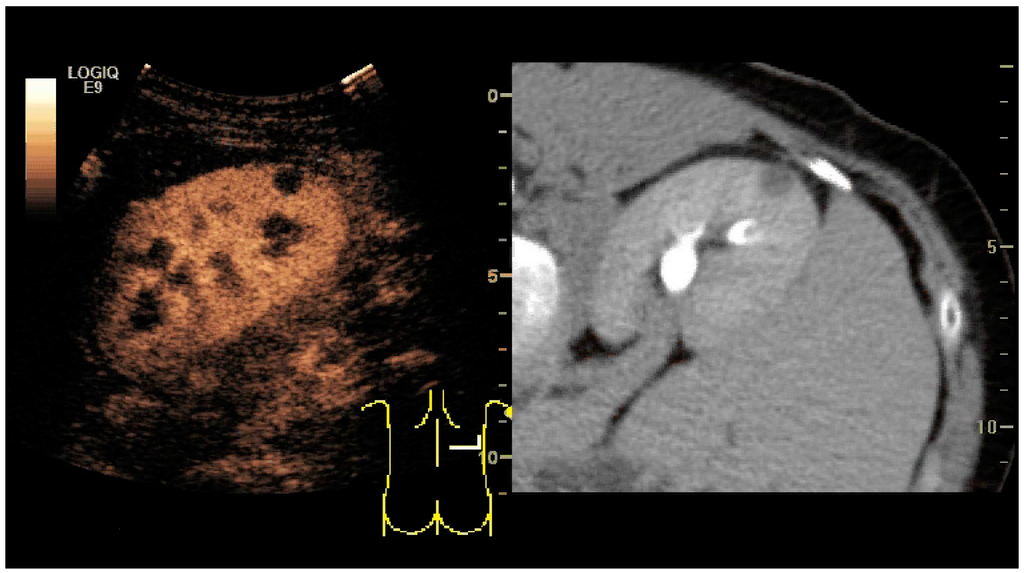

CEUS can evaluate microvasculature, which color Doppler US is unable to detect. In renal US examination, CEUS can be used to differentiate tumor and pseudotumor, such as prominent columns of Bertin. Pseudotumors enhance as adjacent renal tissue. The use of CEUS is recommended in special cases to distinguish between cystic and hypovascularized solid lesions, to characterize complex cysts, abscesses, traumatic lesions and ischemic lesions [35,36]. Solid malignant tumors in the kidney do not exhibit specific enhancement patterns like some liver lesions, and no valid enhancement criteria between benign and malignant renal lesions have been proposed [37,38]. However, CEUS is used in some patients after ablation of renal cell carcinoma to evaluate contrast uptake in the treated area (Figure 30).

Image fusion of ultrasound with a previously recorded dataset of CT or other modalities is rarely used in renal US. Reports on image fusion using CEUS or US combined with CT or MRI in the examination of renal lesions and in difficult US-guided renal interventions have been published (Figure 31) [39]. However, no recommendations have been published so far.

Figure 31. Unspecific cortical lesion on CT is confirmed cystic and benign with contrast-enhanced ultrasound (CEUS) using image fusion.